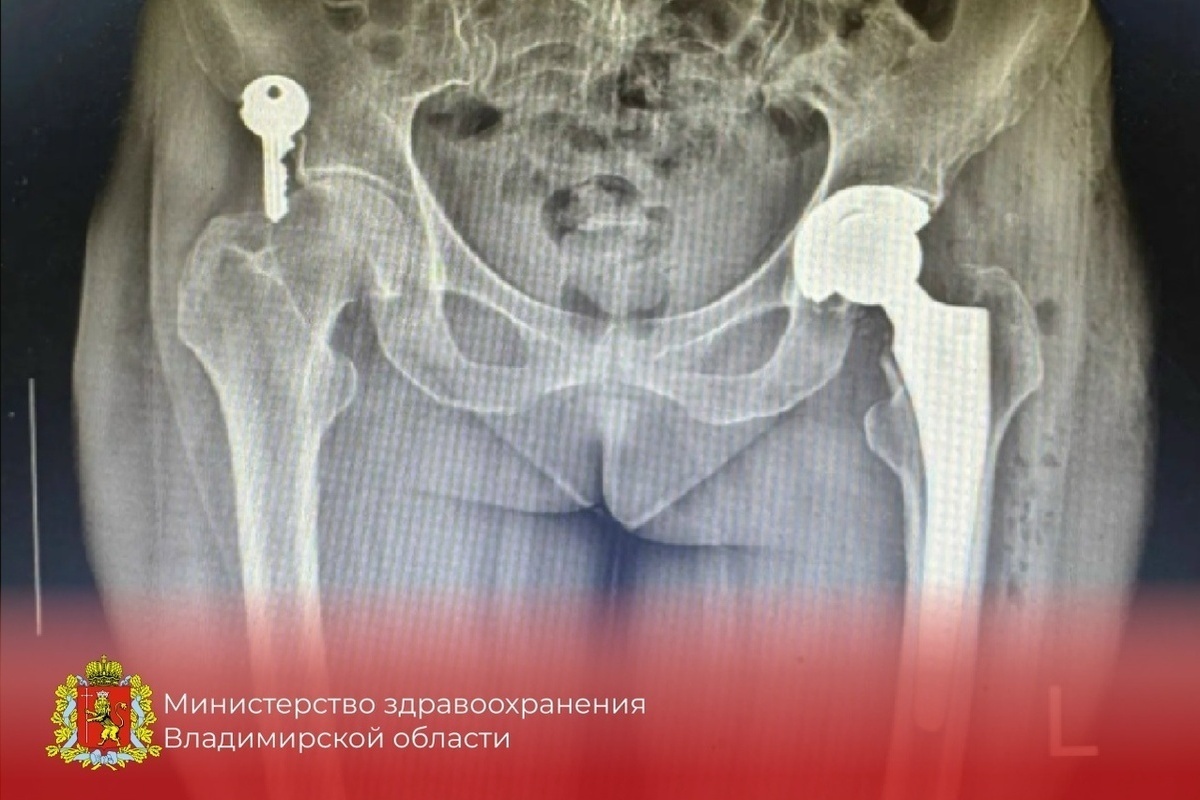

Фото Минздрава Владимирской области

В Ковровской городской больнице освоили современную технологию, меняющую жизни пожилых людей. Местные хирурги теперь проводят сложнейшие операции по замене тазобедренного сустава после переломов.

Освоить передовой метод врачам помог ведущий специалист области Владимир Красильников. Уже проведено более десяти успешных операций. Такие травмы часто случаются у людей старше 60 лет при простом падении дома.

Раньше подобный перелом мог навсегда приковать человека к постели. Новая методика возвращает пациентам возможность ходить и жить полноценно. Это огромный шаг для медицины всего региона, рассказали во владимирском Минздраве.